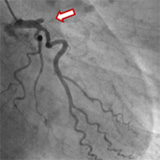

当院の血管撮影装置は同時2方向撮影が可能なバイプレーンシステムの装置です。1回の造影剤の注入で2方向撮影ができるので、少ない造影剤注入で医療情報の多い診断および治療が可能です。

以下の画像は当院で検査された症例の一部です。この他あらゆる部位の検査が可能です。